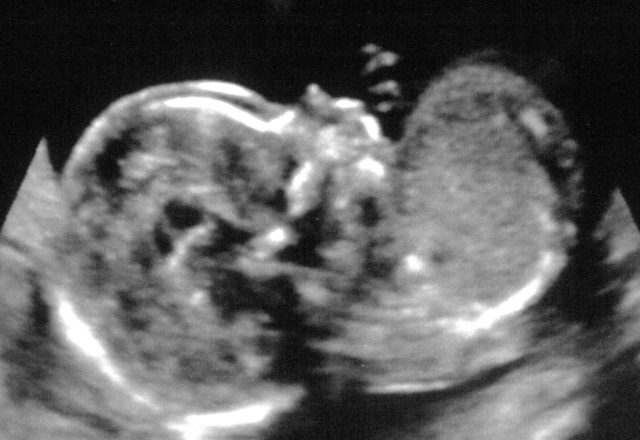

Second Ultrasound

Posted on July 24, 2016July 24, 2016 By Stephen